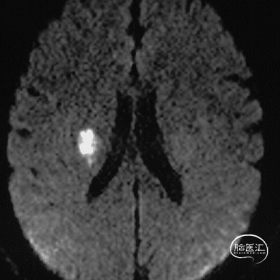

1年前头颅MRI:

DWI可见右侧基底节区新发脑梗,T2 上见额底异常血管流空影。